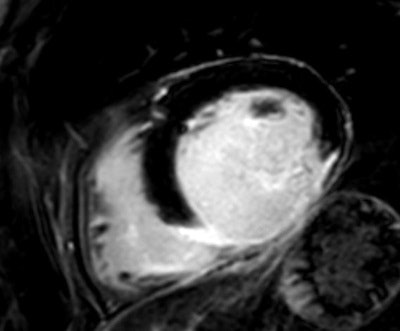

We have tried hard to optimize the MR images of our patients, but the difficulties of respiratory compliance and arrhythmia have limited our success. Detecting scar tissue is one of the most common tasks, and CMR not only reveals the existing damage but also can help to plan further interventions. Signs of inflammation or storage diseases are also often requested, next to a precise volumetry of valvular insufficiencies.

In my practice I have certainly gained more knowledge in working with CMR, and I continue to get more ideas about how to use it to answer specific questions, such as late enhancement for detecting scar tissue, T2-weighted imaging for edema, short axis view, and aortic and pulmonary flow for precise volumetry.